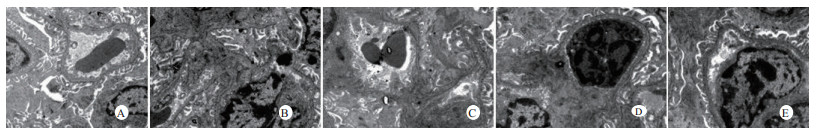

扫描电镜下可见,假手术组肺泡形态完整,肺泡壁光滑;感染性休克组肺泡明显压缩畸形,肺泡隔肿胀、扭曲、隆起;U50488H+感染性休克组肺泡形态大致完整,少数肺泡壁肿胀受损(图 5)。透射电镜下可见,假手术组心肌细胞形态正常;感染性休克组心肌细胞溶解、坏死、肌纤维断裂;U50488H+感染性休克组心肌细胞大致正常,无明显坏死(图 6)。假手术组肝细胞形态正常,毛细胆管未见扩张;感染性休克组肝细胞大片坏死,毛细胆管明显扩张;U50488H+感染性休克组肝细胞形态大致正常,毛细胆管略扩张(图 7)。假手术组肾小管上皮细胞形态狭长,核卵圆形,位于基底部;感染性休克组肾小管上皮断裂,微绒毛缺失;U50488H+感染性休克组肾小管上皮细胞大致正常,微绒毛不平滑,但无明显坏死(图 8)。

| A:假手术组,B:感染性休克组,C:U50488H+感染性休克组,D:nor-BNI+U50488H+感染性休克组,E:nor-BNI+感染性休克组 图 8 肾组织透射电镜检查(×15 000) Fig 8 Transmission electronic microscopic photos of kidney(×15 000) |